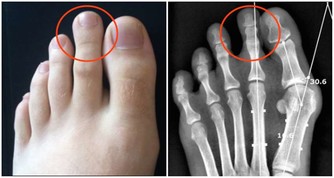

具有泌尿系結石、前列腺

增生、腎臟炎等等可能性。